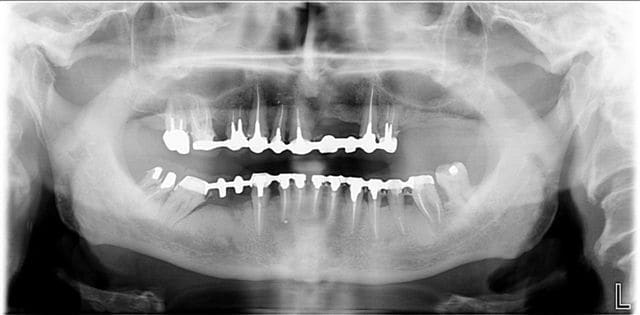

voilà dentiste57 quelques traitements dits globaux, effectivement, il y a eu refonte totale de la bouche avec les endos, la paro, l'occluso ect ... et ceci en 3 mois avec actes groupés sur un patient de 82 ans, j'aurais aimé lui mettre des implants, mais je n'ai pas eu le feu vert du cardiologue.

Après traitement global hby3e2 - Eugenol